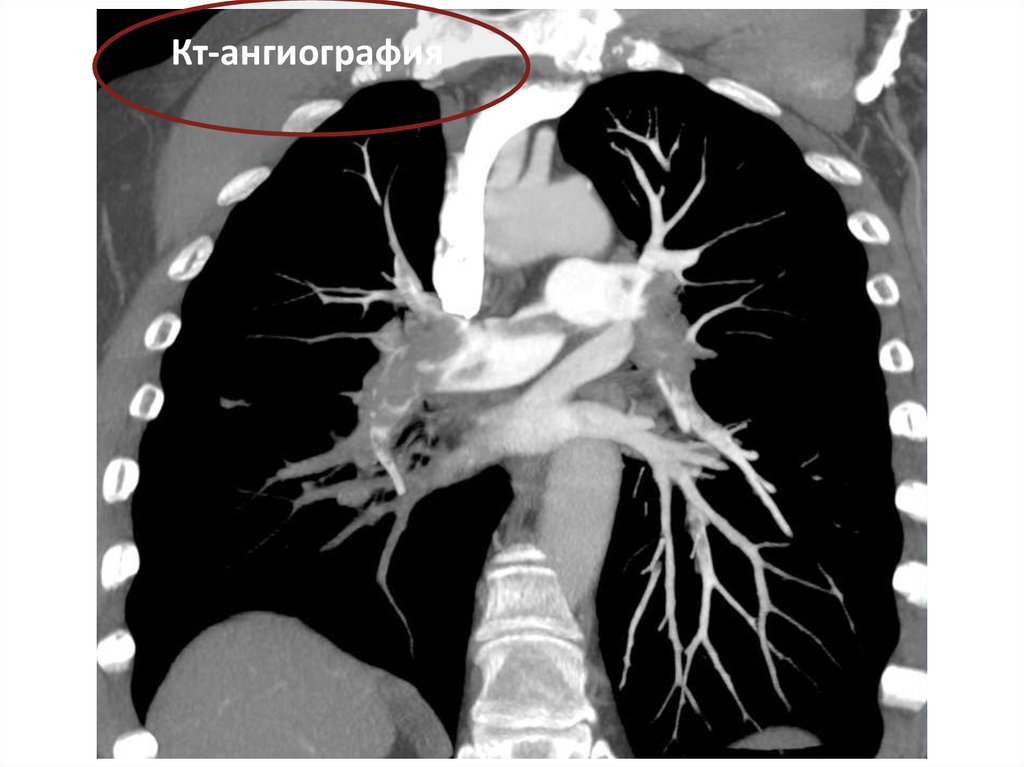

Кт-ангиография